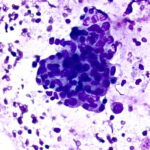

Deposit and stain mode produces two monolayer slides, one unstained and one Diff-Quik(R) stained in 70 seconds.

Stain only mode Diff-Quik(R) stains touch preps and hand prepared smears for immediate high quality immediate staining in 45 seconds.

Adaptable workflow lets you switch between full slide preparation or stain alone, addressing different biopsy needs automatically.